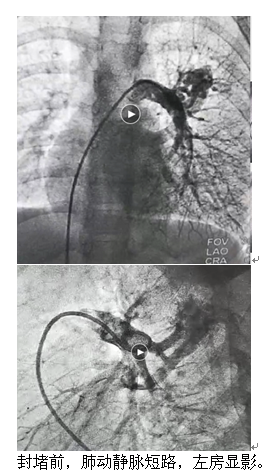

6歲的夕夕(化名)在查體時發(fā)現(xiàn)了肺上長了一團(tuán)迂曲增粗的異常血管影。雖然孩子除了活動耐力略差外,其他方面看起來一切正常,出于謹(jǐn)慎考慮,夕夕媽媽還是帶著孩子來到了青島婦兒醫(yī)院。血管瘤&脈管畸形??漆t(yī)師接診后對孩子進(jìn)行了相關(guān)檢查,診斷夕夕患有“肺動靜脈瘺”!

![1(1)[1].png](/upload/image/20201025/16035889678802733.png)